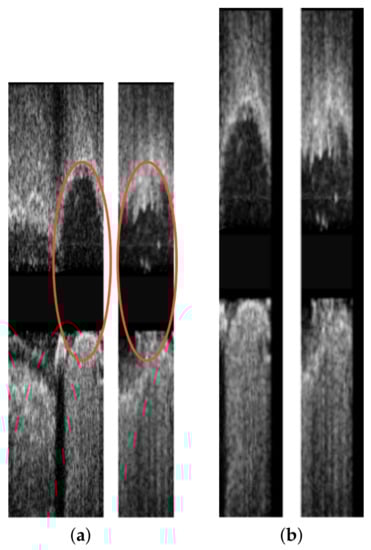

3.2. Longitudinal Registration

- Longitudinal distortion, by randomly repeating an image of the pullbacks to simulate the longitudinal oscillation of the probe. Each image in the pullback had a probability to be repeated, and the times of that repetition was randomly sampled between 1–4 based on the uniform distribution.